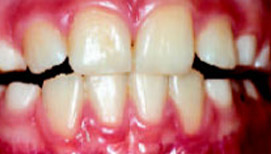

Рис.6: Через 2 недели после начала лечения

Обратное резцовое перекрытие часто сочетается с мезиальным смещением нижней челюсти, при определении конструктивного прикуса нижнюю челюсть необходимо установить в ретро-положение. Кроме того, чтобы найти оптимальное положение зубов, необходимо обратить внимание на характер окклюзионных контактов.